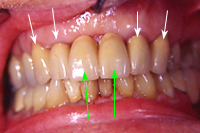

Wieder ein Jahr später machen wir ein Routineröntgenbild der beiden wurzelbehandelten Zähne und stelle beim hinteren Zahn einen beinahe haselnussgrossen Herd fest (Abb. 6). Der Zahn ist zwar schmerzfrei, aber sicher nicht entzündungs- und keimfrei; möglicherweise ist es sogar eine Zyste?

Jetzt erst konnte der operative Eingriff zur Erhaltung des zweithintersten Zahnes geplant werden. Abb. 7 zeigt das Röntgenbild direkt nach dem operativen Eingriff mit den entfernten Wurzelspitzen (schwarzes Loch auf dem Röntgenbild). In Abb. 8 erkennt man 23 Jahre später die beiden wurzelbehandelten Zähne mit absolut gesunden Knochenverhältnissen und schmerzfrei. Es war an diesen Zähnen kein einziger weiterer Eingriff in all den Jahren mehr nötig gewesen.

Warum aber war trotz perfekter Wurzelfüllung am hinteren Zahn noch ein operativer Eingriff nötig? Die Ursache liegt in der Anatomie des Zahnes. Es kommt nicht selten vor, dass neben dem Hauptwurzelkanal sogenannte Seitenkanäle vorhanden sind, die so klein sind, dass sie röntgenologisch nicht sichtbar werden. Diese Seitenkanäle, wie sie schematisch in Abb. 9 links zu sehen sind, gewinnen dann an Bedeutung, wenn der Zahn, wie in diesem Fall, seit längerer Zeit abgestorben ist (erbsengrosses Granulom zu Beginn der Behandlung).

Diese Seitenkanäle waren also bereits zu Beginn der Wurzelbehandlung infiziert, und können weder mechanisch mit Instrumenten aufbereitet noch chemisch mit medikamentösen Einlagen erreicht werden. Der einzig erfolgversprechende Weg ist die Kombination konservativer vorgängiger Wurzelbehandlung mit operativer Entfernung der Wurzelspitze mit den infizierten Seitenkanälen.